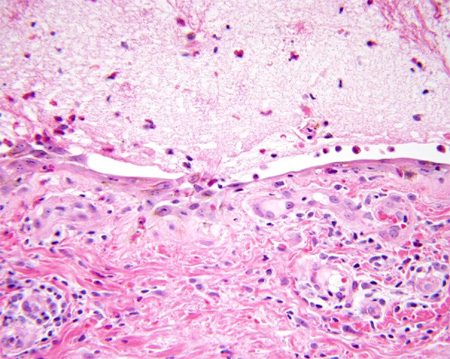

Light microscopy: sub-epidermal blister

From the collection of Dr Vesna Petronic-Rosic